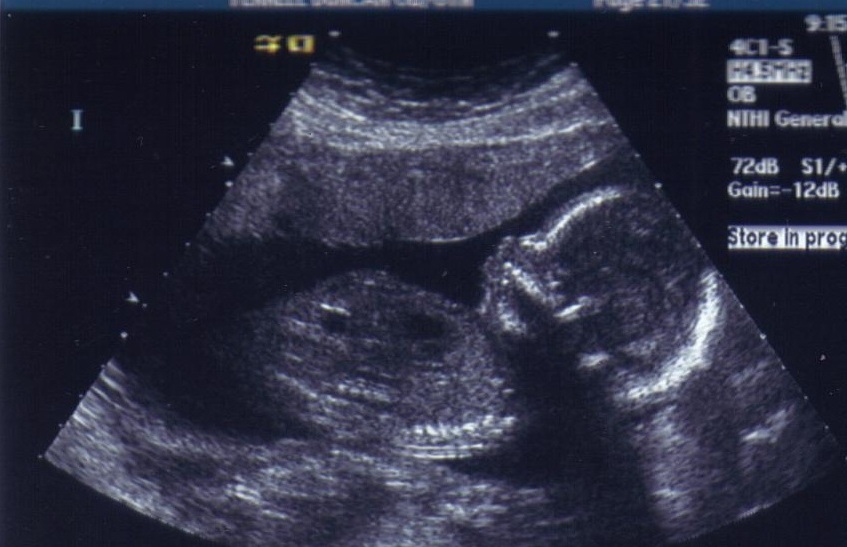

A fabulous profile shot. Cinco has Colton's nose, which is also Lucas and Caleb's nose.